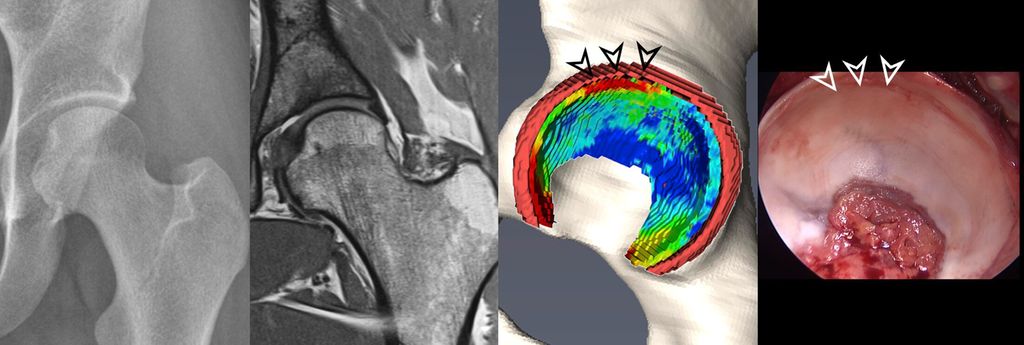

Fig. 2: 3D models of hip cartilage and labrum with color-coded dGEMRIC indices to visualize biochemical cartilage degeneration (red color, black arrowheads) which was confirmed during surgery (white arrowheads).

More recently, we introduced a deep-learning-based approach for automatic segmentation of hip cartilage and labrum using a 3D dGEMRIC sequence (MP2RAGE). The approach allows for automatic and reliable generation of 3D models of hip cartilage and labrum within seconds, and providing both 3D morphologic information of the hip joint as well as color-coded dGEMRIC indices for quantitative analysis of cartilage damage (Fig. 2 & 3).19

As mentioned above, hip MRI assessments are based on selected 2D images. Creating 3D models requires manual segmentation, which involves dividing an image into multiple regions of interest based on pixel properties. This process is done slice by slice, making it very time-consuming and impractical for routine clinical use and is affected by inter-observer variability even when performed by an expert. Deep learning, a branch of machine learning, has shown great promise in automating image segmentation. Convolutional neural networks, particularly those with U-net architecture, are commonly used for this purpose. More recently, the nnU-net, an extension of the U-net, was introduced. It automatically configures itself for biomedical image segmentation and has produced excellent results across various medical imaging tasks.15 Compared to other joints such as the knee automatic segmentation of hip cartilage is more challenging due to its naturally thinner structure and oblique orientation. Previous attempts to automate hip cartilage segmentation were based on small sample sizes and did not include the labrum.16–18 Ideally, combining a 3D analysis of chondro-labral morphology with cartilage composition would enable an improved analysis of chondro-labral dimensions and of the severity of joint damage (Fig. 2 & 3).